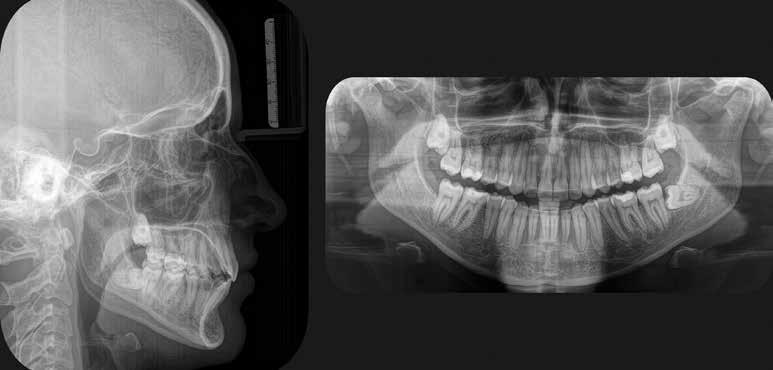

Mind a periapicalis röntgenfelvétel, mind a CBCT-felvétel igazolta, hogy a fragmentum mélyen a gyökércsatorna görbülete mögött, az apikális harmadban helyezkedik el a mesiobuccalis csatornában, valahol a mesiolingualis csatornával történő egyesülés után. Ezenfelül mind a mesialis, mind a distalis gyökércsúcs körül periapicalis gyulladás jelei voltak megfigyelhetőek (1–3. ábra). A betört eszköz nagyjából 5 mm-es hosszúsággal rendelkezett. A mesiolingualis csatornán keresztül a betört fragmentum mellett történő további gyökércsatorna-megmunkálást kockázatosnak ítéltük, mivel nagy esélyt láttunk rá, hogy így a másik eszköz is eltörik, amely pedig a gyökértömés elkészítését nehezítette volna. Azonban a SWEEPS technológiának és a biokerámia sealereknek köszönhetően más megoldási lehetőségek is nyitva álltak előttünk.

A páciens a jobb alsó első nagyőrlőfogából kiinduló közepes erősségű fájdalom miatt kereste fel a rendelőnket. Periapikális röntgen és CBCT-felvétel is készült. Mindkét felvétel a mesiobukkális gyökércsúcs körül található radiolucens elváltozás jelenlétét igazolta. Ezenfelül a mesialis gyökérben két betört eszközdarab is észlelhető volt. Az egyik a középső gyökéri harmadban a gyökérgörbület előtt volt megtalálható, a másik pedig kicsivel a gyökérgörbület után (12–13. ábra).

A CBCT-felvételen a fog mindkét gyökércsúcsa körül radiolucens elváltozás volt észlelhető (26. ábra). Ezenfelül a periapikális felvételen a mesiobuccalis gyökérben egy betört eszközt is felfedeztünk (27. ábra).